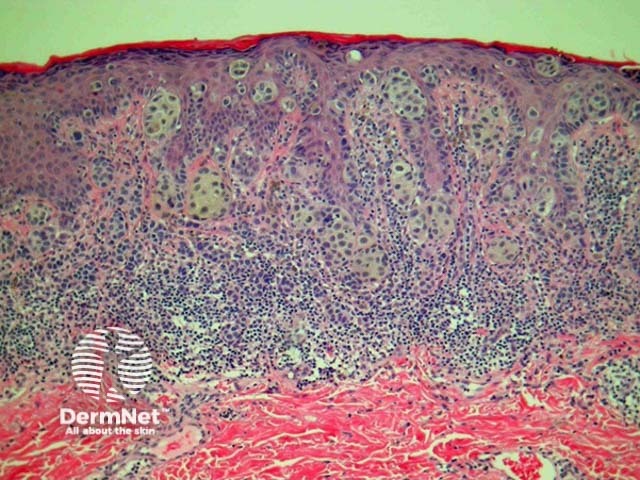

Acral lentiginous melanoma may have spindled or epithelioid cellular morphology. Changes may be subtle with scattered atypical melanocytes located close to the basal layer. Epidermal acanthosis, elongation of rete ridges and extension along sweat ducts are typical features (figure 23).

Figure 23